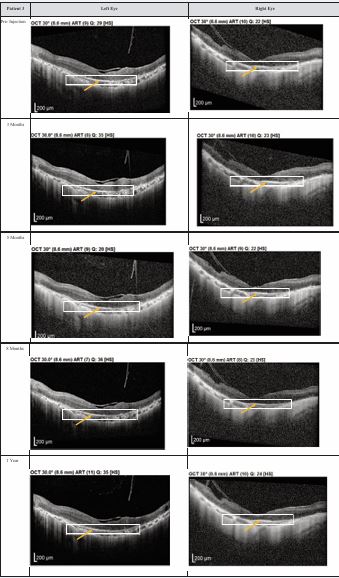

Both patients received a total of seven mesenchymal stem cell (MSC) transplantations, administered every 4-6 weeks, with follow-up from November 2020 to November 2022. Both patients reported no deterioration in vision since the first subtenon implantation in November 2020. Optical coherence tomography (OCT) images consistently demonstrated the maintenance of a hyperreflective region, with no notable increase in intensity. The previously reported improvements in visual function remained stable throughout the two-year follow-up, with no evidence of regression (Figures 1,2).

Figure 1 Optical coherence tomography (OCT) images for both eyes of Patient 1 from pre-injection up to 1 year follow-up. Orange arrow demonstrates the presence of hyperreflective material at the interdigitation area of the photoreceptors at the macula and extramacular region. These were observed and maintained until the last follow-up examination.